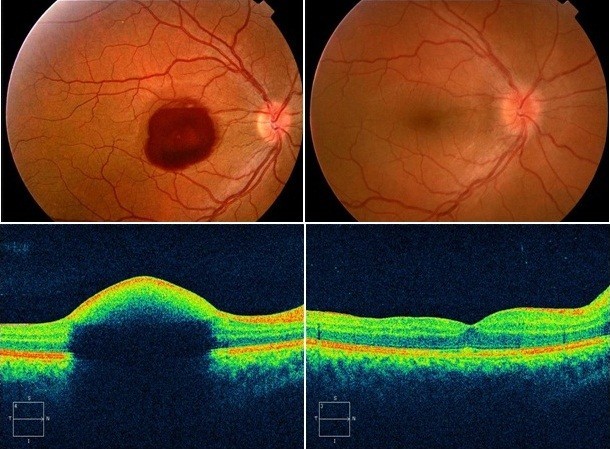

Диагностика зрения: Когерентная томография сетчатки